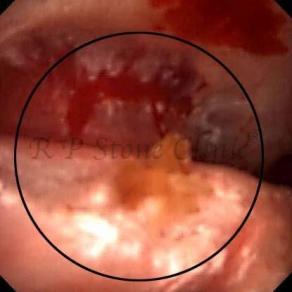

The Below Images Show Small Stones attached to the Renal Papillae.

These images are taken as snap shots from the video recording of RIRS Surgery done at our hospital. These are Randall’s Plaques seen with Digital FLEX XC & Digital FLEX XC S. The cream or whitish patches are seen on the tips of RENAL PAPILLAE as seen in images below.